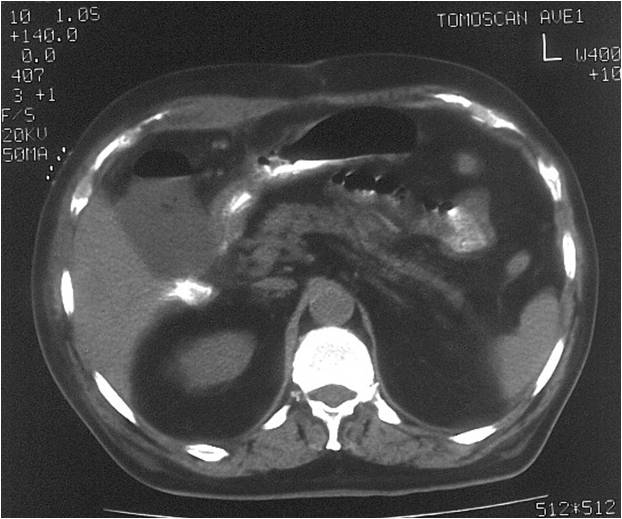

- Right sub diaphragmatic abscess post right hemicolectomy

- Successful drainage